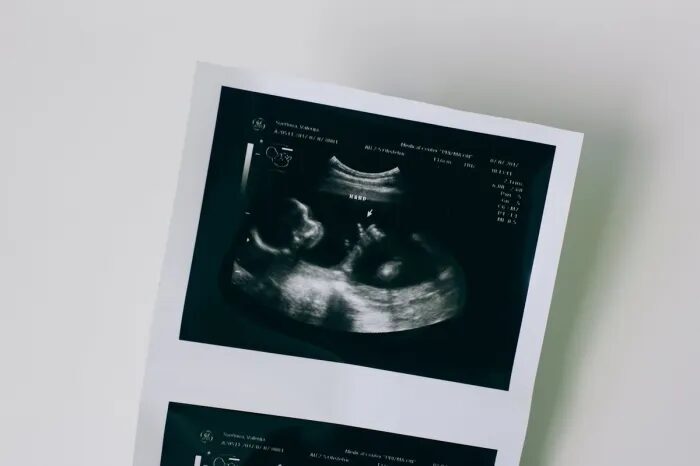

vasa prévia

A condição é descrita como rara, potencialmente fatal, vulnerável à ruptura e com alto risco de morte sem diagnóstico prévio, indicando um forte sentimento negativo associado à sua natureza perigosa.